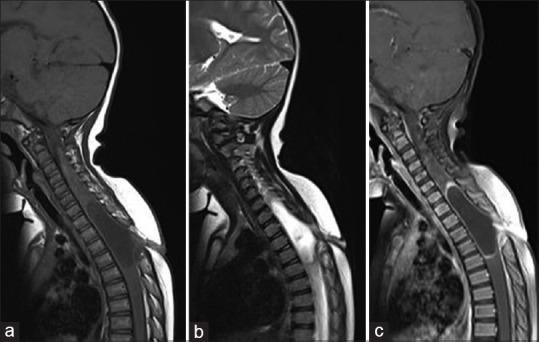

Dorsal dermal sinus (DDS) is an uncommon type of occult spinal dysraphism most often located in the lumbar region. Patients present either due to secondary infection or compression of neural structures by an associated dermoid or epidermoid cyst. We report a rare case of 2-year-old child who presented with progressive paraparesis with magnetic resonance imaging of spine showing a thoracic DDS with an infected intramedullary dermoid cyst. Partial excision of the dermoid cyst and resection of the sinus opening was done with partial clinical improvement postsurgery.